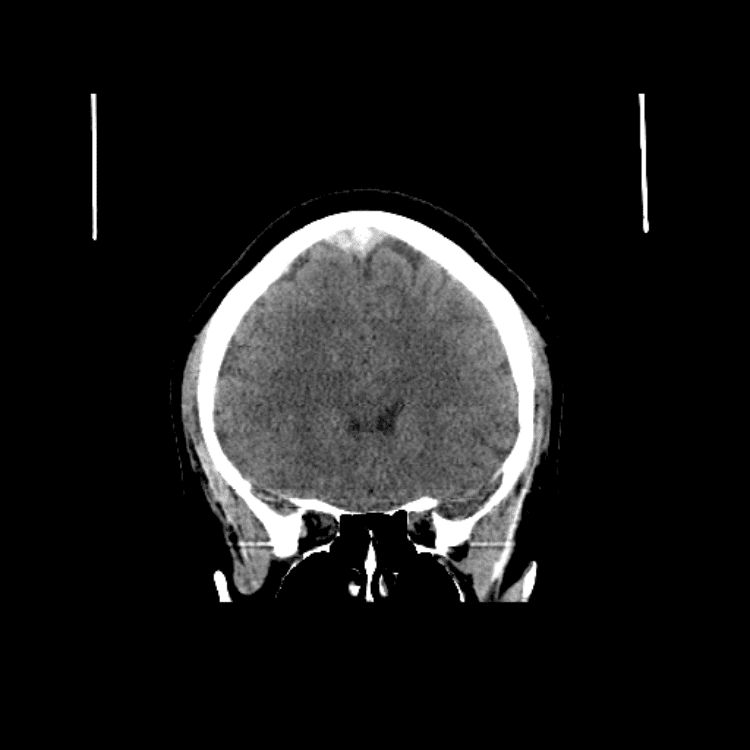

Nontraumatic Brain

Classic